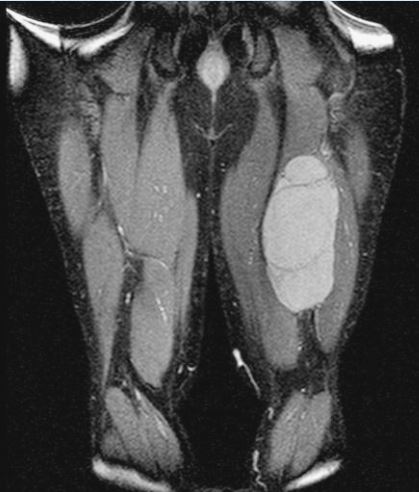

MRI of hamstrings tumor

This is an MRI of the hamstrings tumor. The tumor is the brightened part on the right hand side of the thigh in the image seen.